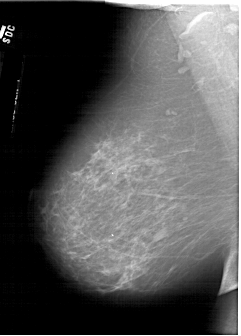

A_1618_1.RIGHT_CC

RIGHT_CC LINES 6616 PIXELS_PER_LINE 3631 BITS_PER_PIXEL 12 RESOLUTION 43.5 OVERLAY

FILE: A_1618_1.RIGHT_CC.OVERLAY

TOTAL_ABNORMALITIES 1

ABNORMALITY 1

LESION_TYPE MASS SHAPE IRREGULAR MARGINS SPICULATED

ASSESSMENT 5

SUBTLETY 3

PATHOLOGY MALIGNANT

TOTAL_OUTLINES 2